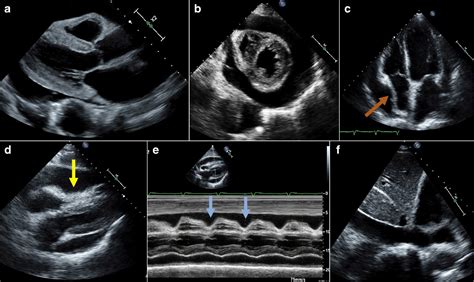

The Importance of Swift Diagnosis

When healthcare providers suspect these symptoms, they move quickly. The primary diagnostic tool used is an Echocardiogram, which provides a real-time ultrasound image of the heart. It allows doctors to visualize the fluid surrounding the heart and observe the mechanical compression of the chambers. In an emergency setting, doctors may not wait for extensive imaging if the patient is unstable; instead, they may perform a procedure called a pericardiocentesis to drain the fluid immediately.